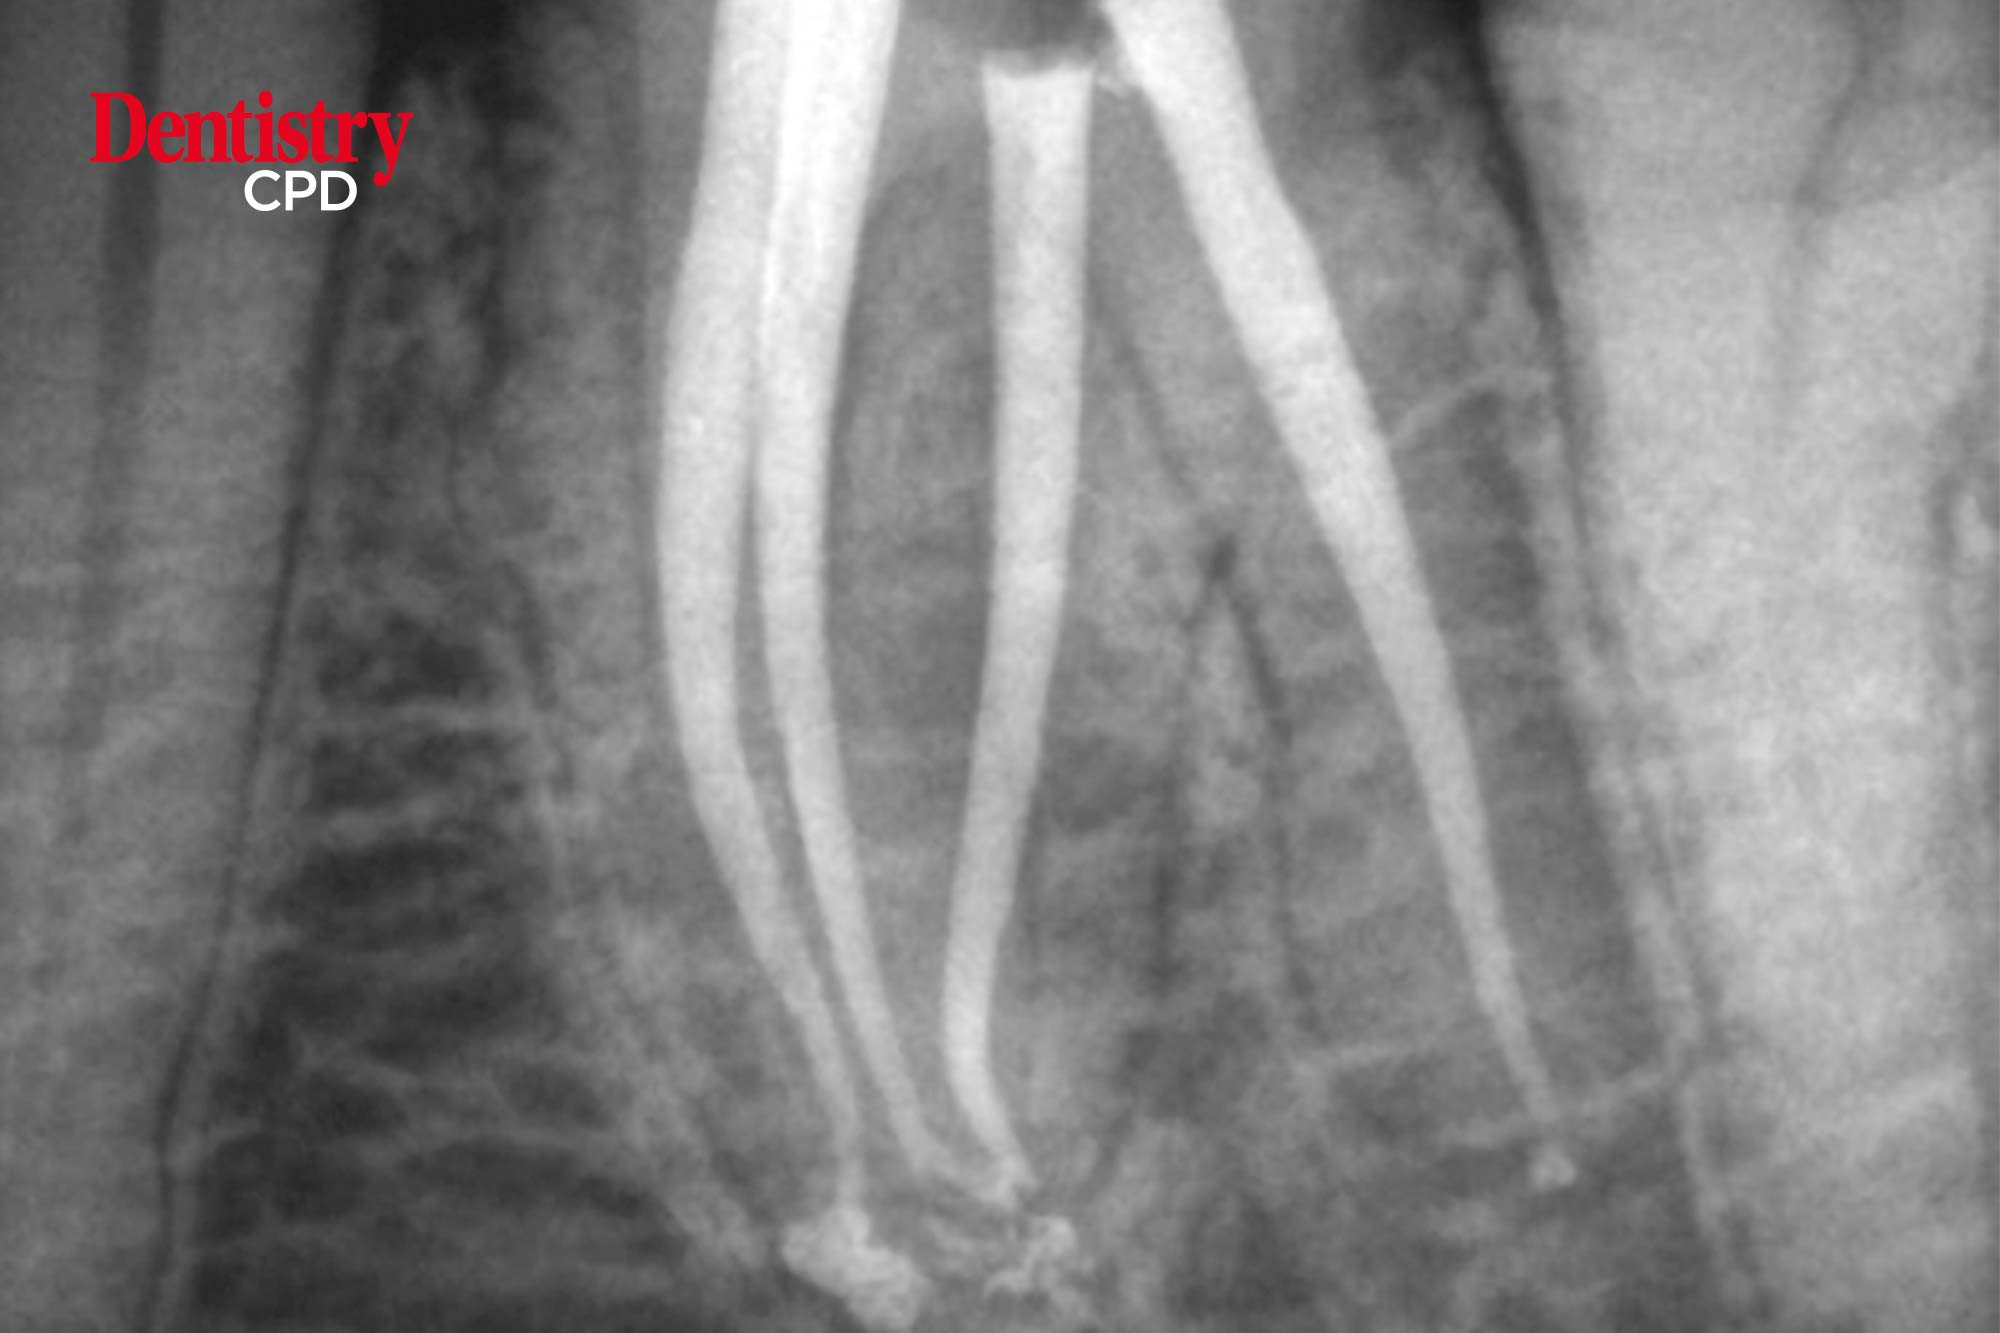

Endodontic masterclass: radix entomolaris

Peet van der Vyver and Martin Vorster kick off a new series by discussing the identification and management of radix entomolaris.